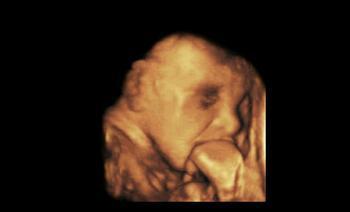

前几天,胡丽生下一名男婴,但检查发现,婴儿大部分颅骨缺失,后脑塌陷,只有少量脑组织,各项生命体征较差,不能存活。胡丽和丈夫只好放弃治疗,把孩子抱回了家。到家后不久,孩子就离开了这个世界,留下悲痛欲绝的胡丽。可是现在后悔也晚了。